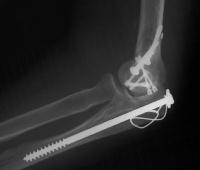

Anatomic reduction.

She began immediate protected motion and discontinued splint use at two weeks, despite recommendations to the contrary. These films are two months postop:

Lateral column not yet fully consolidated on Xray, but clinically healed.